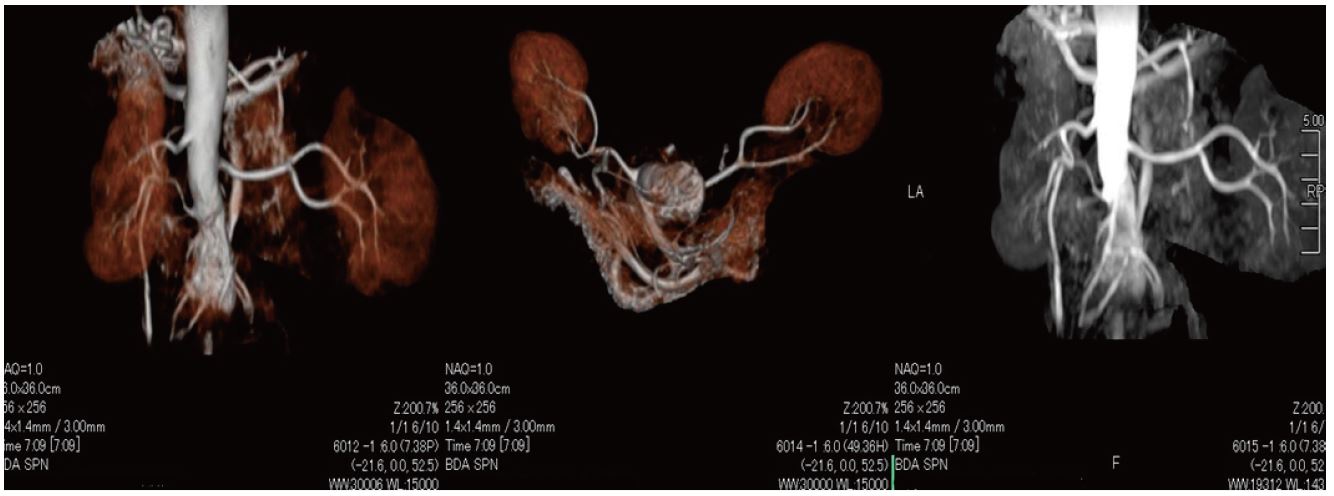

Ангіо-МРТ з використанням методу Time-SLIP

46-річна людина, гіпертонік, ангіо-МРТ з використанням методу Time-SLIP

Метод Time-SLIP

Техніка з використанням парамагнитного контрасту